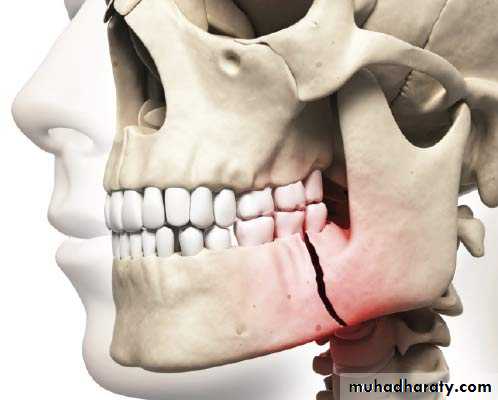

The teeth maybe impacted or malposed and such teeth may predispose to malocclusion , periodontal disturbances, facial pain , bony pathology (cyst), esthetic problems and preventing the erupting on of teeth .9- Tooth in the fracture line of the jaws :

This tooth maybe extracted if :a) It is a source of inflection at the site of the fracture .

b) The tooth itself is fracture .

c) Interfere with fracture reduction .

d) Interfere with healing of fracture .